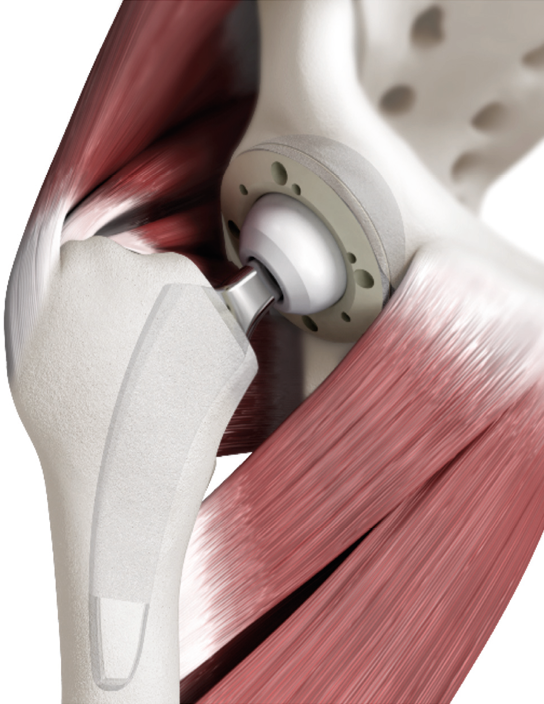

The request for surgical procedures and implants allowing an active, high quality daily life is constantly advancing. Consequently minimally-invasive techniques have been developed, allowing a muscle- and soft-tissue sparing implantation. In modern THA, however, not only the choice of approach determines the postoperative outcome, but also the type of implant. Choosing the adequate stem highly contributes to being able to optimally use minimally-invasive techniques [3], Pfeil J (2010) Minimally Invasive Surgery in Total Hip Arthroplasty [Englisch]. Springer; Auflage: 2010.[4] Kutzner KP, Hechtner M, Pfeil D, et al. (2017) Incidence of heterotopic ossification in minimally invasive short-stem THA using the modified anterolateral approach. Hip Int 0–0. doi: 10.5301/hipint.5000448. (Figure 1).

The positioning of the rounded short stem alongside the calcar curve leads to another attribute of these implants. Unlike in conventional straight stem THA, given the short and rounded design the insertion of the instruments as well as the implantation can be done in the “round-the-corner” technique, sparing the greater trochanter region completely [13], Kutzner KP, Donner S, Schneider M, et al. (2017) One-stage bilateral implantation of a calcar-guided short-stem in total hip arthroplasty. Oper Orthop Traumatol. doi: 10.1007/s00064-016-0481-5.[14] Kutzner KP, Pfeil J (2018) Individualized Stem-positioning in Calcar-guided Short-stem Total Hip Arthroplasty. J Vis Exp. doi: 10.3791/56905(Figure 6). This is convenient, not only regarding the incidence of possible fractures to the trochanter, but also by reducing damage to muscle- and soft-tissue inserting at the piriformis fossa and the greater trochanter, such as the crucial gluteal muscles [8] Mai S, Pfeil J, Siebert W, Kutzner KP (2016) Kalkar-geführte Kurzschäfte in der Hüftendoprothetik - eine Übersicht. OUP 5:342–347. doi: 10.3238/oup.2016.0342–0347..

The usage of minimally-invasive approaches, without transection or damage to the muscles, thus, is clearly facilitated using this technique [3] Pfeil J (2010) Minimally Invasive Surgery in Total Hip Arthroplasty [Englisch]. Springer; Auflage: 2010..